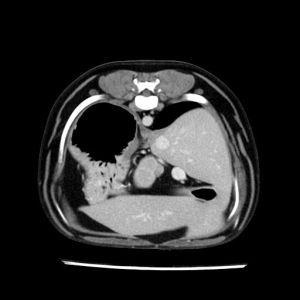

La lesione focale epatica , la ceus,la Tac e il chirurgo .